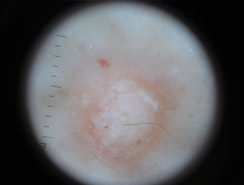

Dermatoscopia

Lo studio e la diagnosi delle neoformazioni cutanee attraverso strumenti specifici indicati per un'analisi delle caratteristiche strutturali superficiali e profonde delle varie neoformazioni cutanee: dermatoscopia, dermalite a luci fotocromatiche, mappatura nevica con videodermatoscopia digitale.

Al fine di una corretta diagnosi dei nevi, e dunque di un'efficace prevenzione da forme tumorali, è indispensabile visionare in profondità i caratteri di ogni formazione nevica. Ciò è reso possibile dall'utilizzo del dermatoscopio e dalla concomitante mappatura nevica, con l' eventuale rimozione chirurgica o laser di: